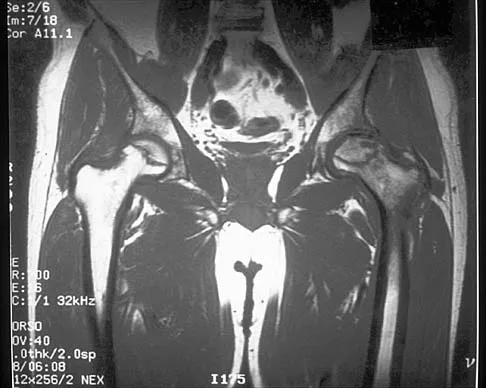

Figure 41 shows the MRI scan of a 39-year-old man who has severe left groin and anterior thigh pain. What is the most likely diagnosis?

Explanation